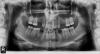

Мне 21 год, у меня всего 22 зуба, остальные просто не выросли, даже не было зачатков.

Несколько лет назад носил брекеты, потом брекеты сняли и сказали носить пластинку со специальным винтом, который толкает жевательные зубы на правой стороне и освобождает место, чтобы хватило для двух имплантов.

Снимок (приложен внизу) я делал уже после того как сняли брекеты, врач ничего на зубы после снятия брекетов не клеил, и поскольку пластинка штука не идеальная, зубы впереди начали немного раздвигаться. Но в целом сейчас положение такое же как на снимке, я каждый день на ночь одеваю пластинку.

Когда я пошел потом на консультацию к имплантологу, он сказал что ортодонтическое лечение не закончено, нужно разворачивать клык внизу, освобождать дальше место для двух зубов справа и занижать 5ки снизу и т.д.